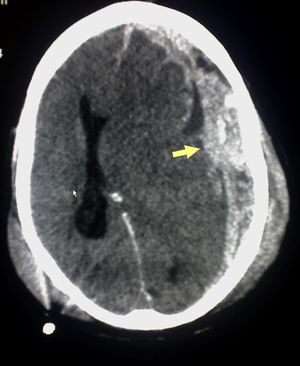

يعتمد رئيساً على تصوير الدماغ (التصوير الطبقي المحوري والرنين المغنطيسي MRI)، وفيه يظهر النزف عادة على شكل تجمع هلالي بين الجمجمة والدماغ.